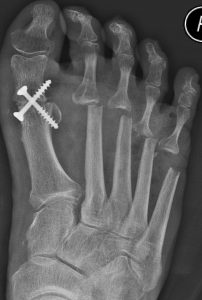

Update orthopädische Rheumatologie – Bis wann ist der Gelenkerhalt möglich?31. August 2022 Abb. 1: Zottige, hoch aktive Synovialitis im dorsomedialen Rezessus eines linken Kniegelenkes. (Bild: Gaulke) Die Entscheidung zwischen Erhalt, Ersatz, Resektion oder Versteifung eines Gelenkes bei entzündlich-rheumatischen Erkrankungen ist von vielen Faktoren abhängig und sollte von erfahrenen Rheumachirurgen vorgenommen werden. Im Folgenden gibt der Experte und derzeitige Präsident der Deutschen Gesellschaft für Orthopädische Rheumatologie (DGORh) eine Übersicht zu den aktuellen Optionen. Vor der Ära der Biologika war der Gelenkerhalt häufig nur durch eine totale Synovialektomie möglich. Bei noch intaktem Gelenk spricht man dabei von einer Frühsynovialektomie, liegen bereits Gelenkschäden vor, so wird die Prozedur als Spätsynovialektomie bezeichnet. Durch die Entfernung der Gelenkinnenhaut mit anschließender Radiosynoviorthese war es in vielen Fällen möglich, über Jahre die Gelenkzerstörung aufzuhalten oder zumindest zu verlangsamen und das Gelenk zu erhalten. Seit Einführung der Biologika (bDMARDs) und der small molecules (tsDMARDs) schreitet die Gelenkzerstörung sehr viel langsamer voran als unter den klassischen Basistherapeutika (csDMARDs). Das therapeutische Fenster für gelenkerhaltende Eingriffe ist somit länger geöffnet, was als günstig anzusehen ist. Dem entgegen steht allerdings, dass die Entzündung des Gelenkes unter wirksamer medikamentöser Therapie häufig schmerzarm oder -frei und daher vom Patienten unbemerkt verläuft, sodass sich das länger geöffnete therapeutische Fenster für gelenkerhaltende Eingriffe heute öfter ungenutzt schließt als früher, als die entzündeten Gelenke stark schmerzten (Abb. 1). Die Patienten entwickeln heutzutage häufig erst Beschwerden, wenn das Gelenk bereits stark zerstört ist und dann nur noch Resektionsarthroplastiken, Arthrodesen und Endoprothesen zur Schmerzbefreiung möglich sind. Um das primäre Ziel des Gelenkerhaltes zu erreichen, ist es daher unbedingt erforderlich, Hausärzte, internistische und orthopädische Rheumatologen sowie die Patienten selbst dafür zu sensibilisieren, sich bei persistierenden Gelenkschwellungen frühzeitig beim orthopädischen Rheumatologen vorzustellen, um durch eine zeitnahe Synovialektomie die Gelenke möglichst lange erhalten zu können. Da durch die bDMARD- und tsDMARD-Therapie die Entzündung häufig beruhigt oder stark reduziert werden kann, kommen für diese Patienten, vor allem an der unteren Extremität, auch achskorrigierende Osteotomien zur Anwendung, welche früher der Arthrose vorbehalten waren. Abb. 2: Klassische Vorfußkorrektur bei entzündlich-rheumatischen Erkrankungen: Tarsometatarsale I-Arthrodese und Resektionsarthroplastik Zehengrundgelenke II–V nach Hoffmann/Tillmann rechts. Abb. 3: Vorfußkorrektur analog zum Senk-Spreiz-Fuß bei beruhigter Krankheitsaktivität: Tarsometatarsale I-Arthrodese, Modifizierte Chevronosteotomie und Verkürzungsosteotomien MFK II und III rechts. Auch am Fuß haben die varisierende Osteotomie des Fersenbeins gegenüber der subtalaren Arthrodese und die Verkürzung der Mittelfußknochen bei Überlänge gegenüber den Resektionsarthroplastiken auch bei entzündlich-rheumatischen Erkrankungen an Bedeutung gewonnen. Die Resektionsarthroplastik der Zehengrundgelenke entspricht einer funktionellen Vorfußamputation, das heißt die Zehen sind zwar erhalten, können aber nicht kraftvoll bewegt werden (Abb. 2). Bei erhaltenen Gelenken hingegen ermöglicht die kräftige aktive Beugung der Zehen einen physiologischeren dynamischen Gang (Abb. 3). Wie lange ein Gelenkerhalt trotz bestehender Schäden möglich ist, hängt maßgeblich von der Belastung des Gelenkes ab, so tolerieren die Gelenke der oberen Extremitäten deutlich stärkere sekundäre Arthrosen als die belasteten Gelenke der unteren Extremitäten. Da im Rahmen einer totalen Synovialektomie immer auch eine Denervation des Gelenkes durch Resektion der in die Synovialis endenden Nerven erfolgt, können beispielsweise an der Schulter bei intakter Rotatorenmanschette auch dann noch Spätsynovialektomien sinnvoll durchgeführt werden, wenn die knöchernen Konturen des Humeruskopfes und des Glenoids, trotz des Verlustes des Knorpels, erhalten sind. Auch am Ellenbogengelenk kann trotz vollständigen Verlustes des Knorpels noch eine gute schmerzfreie Funktion in vielen Fällen wiederhergestellt werden. Insbesondere im Hinblick auf die relativ hohe Komplikationsrate der Ellenbogenendoprothesen sollten hier die Möglichkeiten der gelenkerhaltenden Eingriffe ausgeschöpft und die Indikation zur Endoprothese streng gestellt werden. Am Handgelenk kann bei geringer Krankheitsaktivität durch Sehnentransposition und Teilarthrodesen häufig eine Reposition und Stabilisierung des Karpus erzielt werden. Durch Vermeidung der totalen Arthrodese des Handgelenkes bleibt dem Patienten eine Restbeweglichkeit erhalten, welche vor allem für die Körperpflege sehr wertvoll ist. Aufgrund der geringen Haltbarkeit der Swanson-Spacer an den Fingergrundgelenken sollte auch hier bei beginnender Subluxation mit aktiv überwindbarer Schwanenhalsdeformität durch das Littler-Release mit Synovialektomie eine Stabilisierung der Fingergrundgelenke unter Gelenkerhalt durchgeführt werden. An den Mittelgelenken der Finger gestaltet sich aufgrund des kleinen Gelenkraumes und des engen Gelenkspaltes die totale Synovialektomie häufig schwierig. Neue Therapiekonzepte mit Oberflächenersatzprothesen an den Fingermittelgelenken kommen hier bei Kongruenzverlust durch stärkere knöcherne Arrosionen zunehmend zur Anwendung. An den Endgelenken ist die Synovialektomie ohne Versteifung in der Regel nicht erfolgversprechend. Am Unterarm kann auch bei entknorpelten Gelenkflächen ein Erhalt des Radius- und Ulnaköpfchens bei geringer Krankheitsaktivität zunehmend angestrebt werden. Dies verhindert die Instabilität der Aufhängung des Radius an der Elle, da die Membrana interossea gespannt bleibt. An der unteren Extremität toleriert das Hüftgelenk die Destruktion am geringsten. Synovialektomien an der Hüfte können arthroskopisch durchgeführt werden. Bei stärkeren Destruktionen sollte jedoch großzügig der endoprothetische Ersatz erfolgen. Am Kniegelenk kann bei Achsfehlstellung durch eine Korrektur der Achse der asymmetrische mechanische Reiz vom Gelenk genommen werden. Diese sollte aber immer dann, wenn eine Synovialitis vorliegt, mit einer totalen Synovialektomie kombiniert werden. Am oberen Sprunggelenk wird die arthroskopische Synovialektomie häufig mit einer Resektion von Osteophyten kombiniert, welche die Dorsalextension einschränkten. Solange der Talus nicht in das Pilon tibiale einbricht, kann auch hier der Versuch des Gelenkerhaltes unternommen werden. Bei einer Instabilität des Subtalargelenkes sollte sehr genau abgewogen werden, ob eine varisierende Verschiebeosteotomie des Kalkaneus zu einer ausreichenden Stabilisierung führt. Ansonsten sollte hier der subtalaren Arthrodese der Vorzug gegeben werden. Im Großzehengrundgelenk kann eine Synovialektomie mit Cheilektomie zu guten Ergebnissen führen, wenn die Grunderkrankung ausreichend beherrscht ist. An den MTP II–V kommt der plantaren Bursitis, welche das plantare Fettgewebe zerstört, eine größere Bedeutung als der Arthritis des Gelenkes zu. Hier sollte eine Verkürzungsosteotomie der Mittelfußknochen unter Erhalt der Gelenke nur dann durchgeführt werden, wenn die Grunderkrankung durch die Immunsuppression ausreichend beherrscht ist und keine plantaren Bursitiden vorliegen. Eine Synovialektomie an den Zehengrundgelenken ohne Resektion der plantaren Bursae ist in der Regel nicht zielführend, da mit einem frühen Rezidiv zu rechnen ist. Fazit Zusammenfassend bestehen unter guter Krankheitsberuhigung zunehmend auch für extraartikuläre Korrekturen gute Indikationen. Bei hoher entzündlich-rheumatischer Krankheitsaktivität hingegen werden mit den klassischen Gelenkoperationen bessere Ergebnisse erzielt. Zwischen diesen Optionen abzuwägen bedarf großer Erfahrung, weshalb die Behandlung in einem Spezialzentrum für operative Rheumachirurgie empfohlen wird. Eine Liste dieser Kliniken finden Sie unter www.dgorh.de Autor: Prof. Dr. med. Ralph GaulkeUnfallchirurgische Klinik, Sektion Obere Extremität, Fuß- und Rheumachirurgie Medizinische Hochschule HannoverCarl-Neuberg-Str. 1, 30625 Hannover